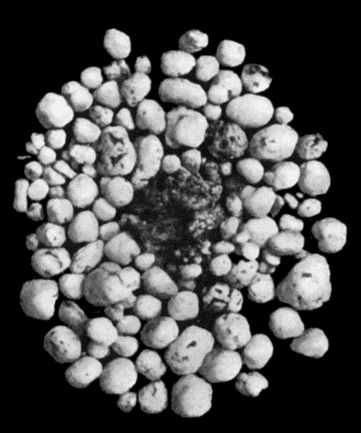

| 30. | Colony of Actinomyces | 126 |

| 114. | Section through Gouty Bursa | 428 |